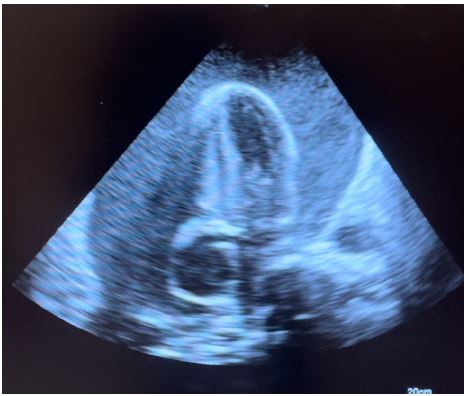

Figure 1: Subcostal echo view showing massive pericardial effusion.

Transthoracic echocardiography is the best diagnostic imaging, useful in diagnosis and management of tuberculous pericardial effusion. Echocardiography can provide an estimate of the size of effusions. Generally, the size of the effusion on echocardiography indicates the volume of pericardial fluid as follows: small (<10 mm), which corresponds to 50-100 mL pericardial fluid; moderate (10-20 mm), corresponding to 100 - 500 mL pericardial fluid and large (>20 mm), corresponding to >500 mL pericardial fluid [19] . The study of Diakité et al. showed 18% of moderate abundance and 81% of high abundance among 49 cases of tuberculous pericarditis [6].